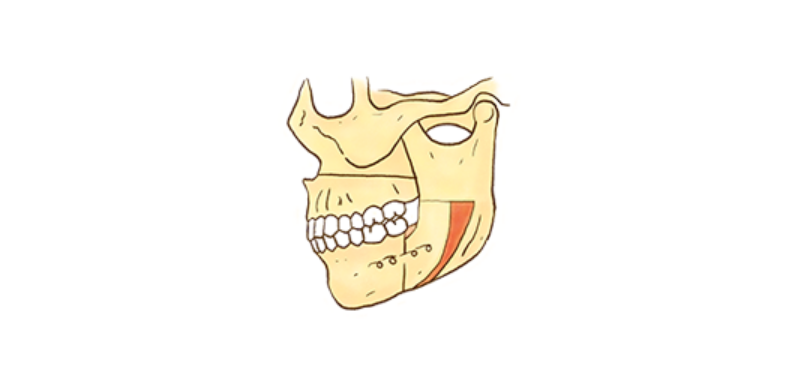

수술을 위한 교정치료

주걱턱, 무턱증, 안면비대칭 등 턱뼈 자체의 부조화가 심한 경우 치열교정 만으로는 치료가 어려운 경우도 있습니다. ​​​​​​​

이때는 치열교정과 턱 수술을 병행해야 합니다.

수술 교정

일반 교정치료만으로는 개선이 어려운 골격을 변화시키는 심미성이 우수한 교정 프로그램입니다.

턱 수술과 교정치료를 병행하여 치료하는 것으로 주걱턱, 안면 비대칭, 무턱, 돌출입 등과 같은 증례에서 주로 이루어지며,

하악 수술 또는 양악 수술이 시행됩니다.